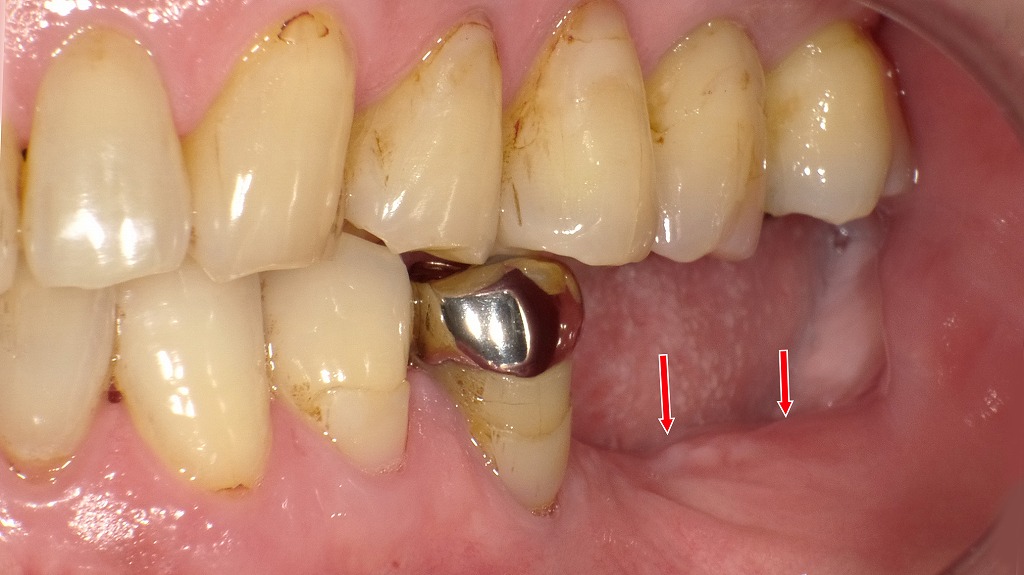

この画像は、左下の臼歯部(第1大臼歯=6番、第2大臼歯=7番)相当部の欠損を示しています。以下に詳しく解説します。

🦷 現状の口腔内所見

- 赤矢印部(左下6番・7番相当部):

歯が欠損しており、歯槽堤(あごの骨と歯ぐき)が軽度に吸収しています。

粘膜面は比較的滑らかで、インプラント埋入に適した状態に見えます。 - 隣接歯(左下5番):

金属冠(クラウン)が装着されています。隣在歯として、インプラントのガイド基準となる重要な支点になります。 - 上顎の対合歯:

長期間の欠損による咬合変化が僅かに推察されます。咬合高径の回復や咬み合わせの再構成が必要となる場合があります。 - 歯肉の状態:

全体的に軽度の歯垢沈着が見られ、歯肉縁がやや炎症性変化を示しています。インプラント前にはプラークコントロールの徹底が推奨されます。

💡 治療計画の概要

- 診断:左下6・7番欠損

- 治療方針:

インプラントによる咬合回復を計画。

具体的には、6番と7番部にそれぞれ1本ずつインプラントを埋入し、2本の上部構造(連結または単独クラウン)で補綴予定。 - 術式の想定:

骨幅と粘膜厚から判断して、2回法によるインプラント埋入(一次手術:埋入 → 二次手術:ヒーリングキャップ装着)が適応と考えられます。

🔍 注意・補足事項

- 骨量が不足している場合は、GBR(骨造成)などの併用を検討。

- 咬合圧の分散と骨吸収抑制の観点から、6・7番ともに埋入するのが望ましい。

- 術前にパノラマレントゲンとCT撮影を行い、下歯槽神経管との距離を十分確認する必要があります。